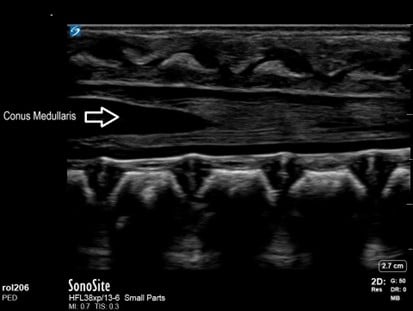

None of this has prevented the development of more distinct adaptations of POCUS for the pediatric population. Unique applications in children have included infant lumbar punctures guided by direct visualization of the cauda equina, protocols for intussusception, algorithms to confirm endotracheal tube placement, and the expansion of ultrasound first approach to appendicitis among many more yet at bedside. Bedside experience coupled with research has uncovered unique advantages our smaller patients offer in regard to image depth and clarity for structures not well imaged in adults. As a result, what has followed includes specific probe advancements allowing access to higher frequency and smaller footprints. This has allowed visualization of submillimeter neonatal vasculature and the ability to peer between infant ribs and tailor neonatal presets.

Figure 3. Conus medullaris visualized in long axis prior to lumbar puncture in infant